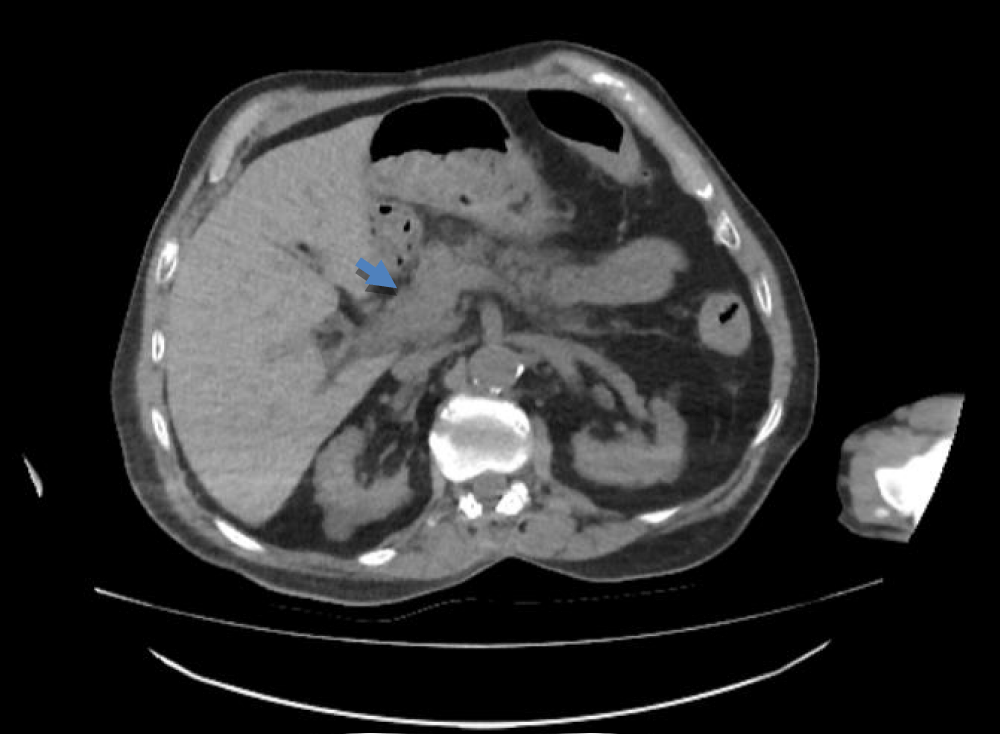

The patient’s oral intake was discontinued in the emergency department, pantoprazole was initiated, and 2000 cc of isotonic fluid was administered for hydration. Tramadol was used as needed for pain management. Laboratory results showed elevated amylase and lipase levels, a negative CRP and a creatinine level consistent with the baseline. Additionally, hypercalcemia and leukocytosis were not detected; the patient had normochromic normocytic anemia consistent with chronic disease anemia (Table 1). Abdominal computed tomography (CT) showed edema in the head of the pancreas, with no abnormalities detected in the bile ducts (Figure 1).

Figure 1: Edematous appearance of the pancreas on abdominal computed tomography.